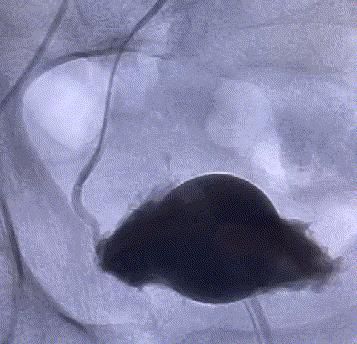

随後,李旭丹主任攜手胡志華主任爲患者實施介入治療,采用改良Seldinger法穿刺股動脈,在DSA引導下經動脈自然腔道,将微導管分别送達雙側髂内動脈進行造影,觀察雙側前列腺動脈分布情況,将微導管超選擇至雙側前列腺動脈,準确置入PVA栓塞材料,成功阻斷前列腺的營養供給,順利完成了治療。

介入治療後第1天,患者排尿困難即得到緩解。因無需切開任何組織,比傳統前列腺微創手術更微創,2天後患者就順利出院了。後續随訪,患者均反饋排尿功能正常,狀态良好,并對李旭丹主任團隊的精湛技術連連點贊。

△術後,前列腺供血動脈被成功阻斷。